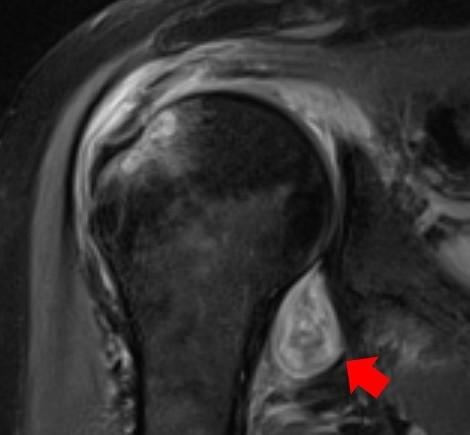

Hình ảnh MRI trên vai một bệnh nhân Covid-19. Mũi tên màu đỏ là vị trí viêm khớp. Sau khi nhiễm nCoV, bệnh nhân bị đau vai, viêm khớp dạng thấp kéo dài dù các triệu chứng khác đã hết. Ảnh: Đại học Northwestern.

Bà cũng cho biết hình ảnh X-quang cho nhóm chuyên gia biết liệu đau cơ, khớp có liên quan SARS-CoV-2 hay không. Và nó khác với hiện tượng đau nhức cơ thể do cúm thông thường như thế nào.

Theo vị chuyên gia này, hình ảnh CT, MRI, X-quang mà nhóm thu được cũng lý giải vì sao một người có triệu chứng đau cơ xương khớp kéo dài sau Covid-19. Trong một số trường hợp, bác sĩ X-quang có thể đề xuất chẩn đoán người mắc Covid-19 dựa trên những hình ảnh này, nhất là với trường hợp chưa thể sàng lọc họ có nhiễm virus hay chưa.